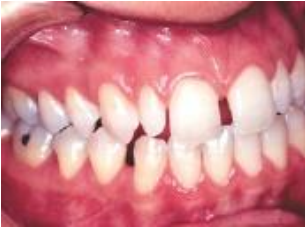

Observe a imagem, abaixo:

À imagem, observa-se, microdontia do elemento

dental: